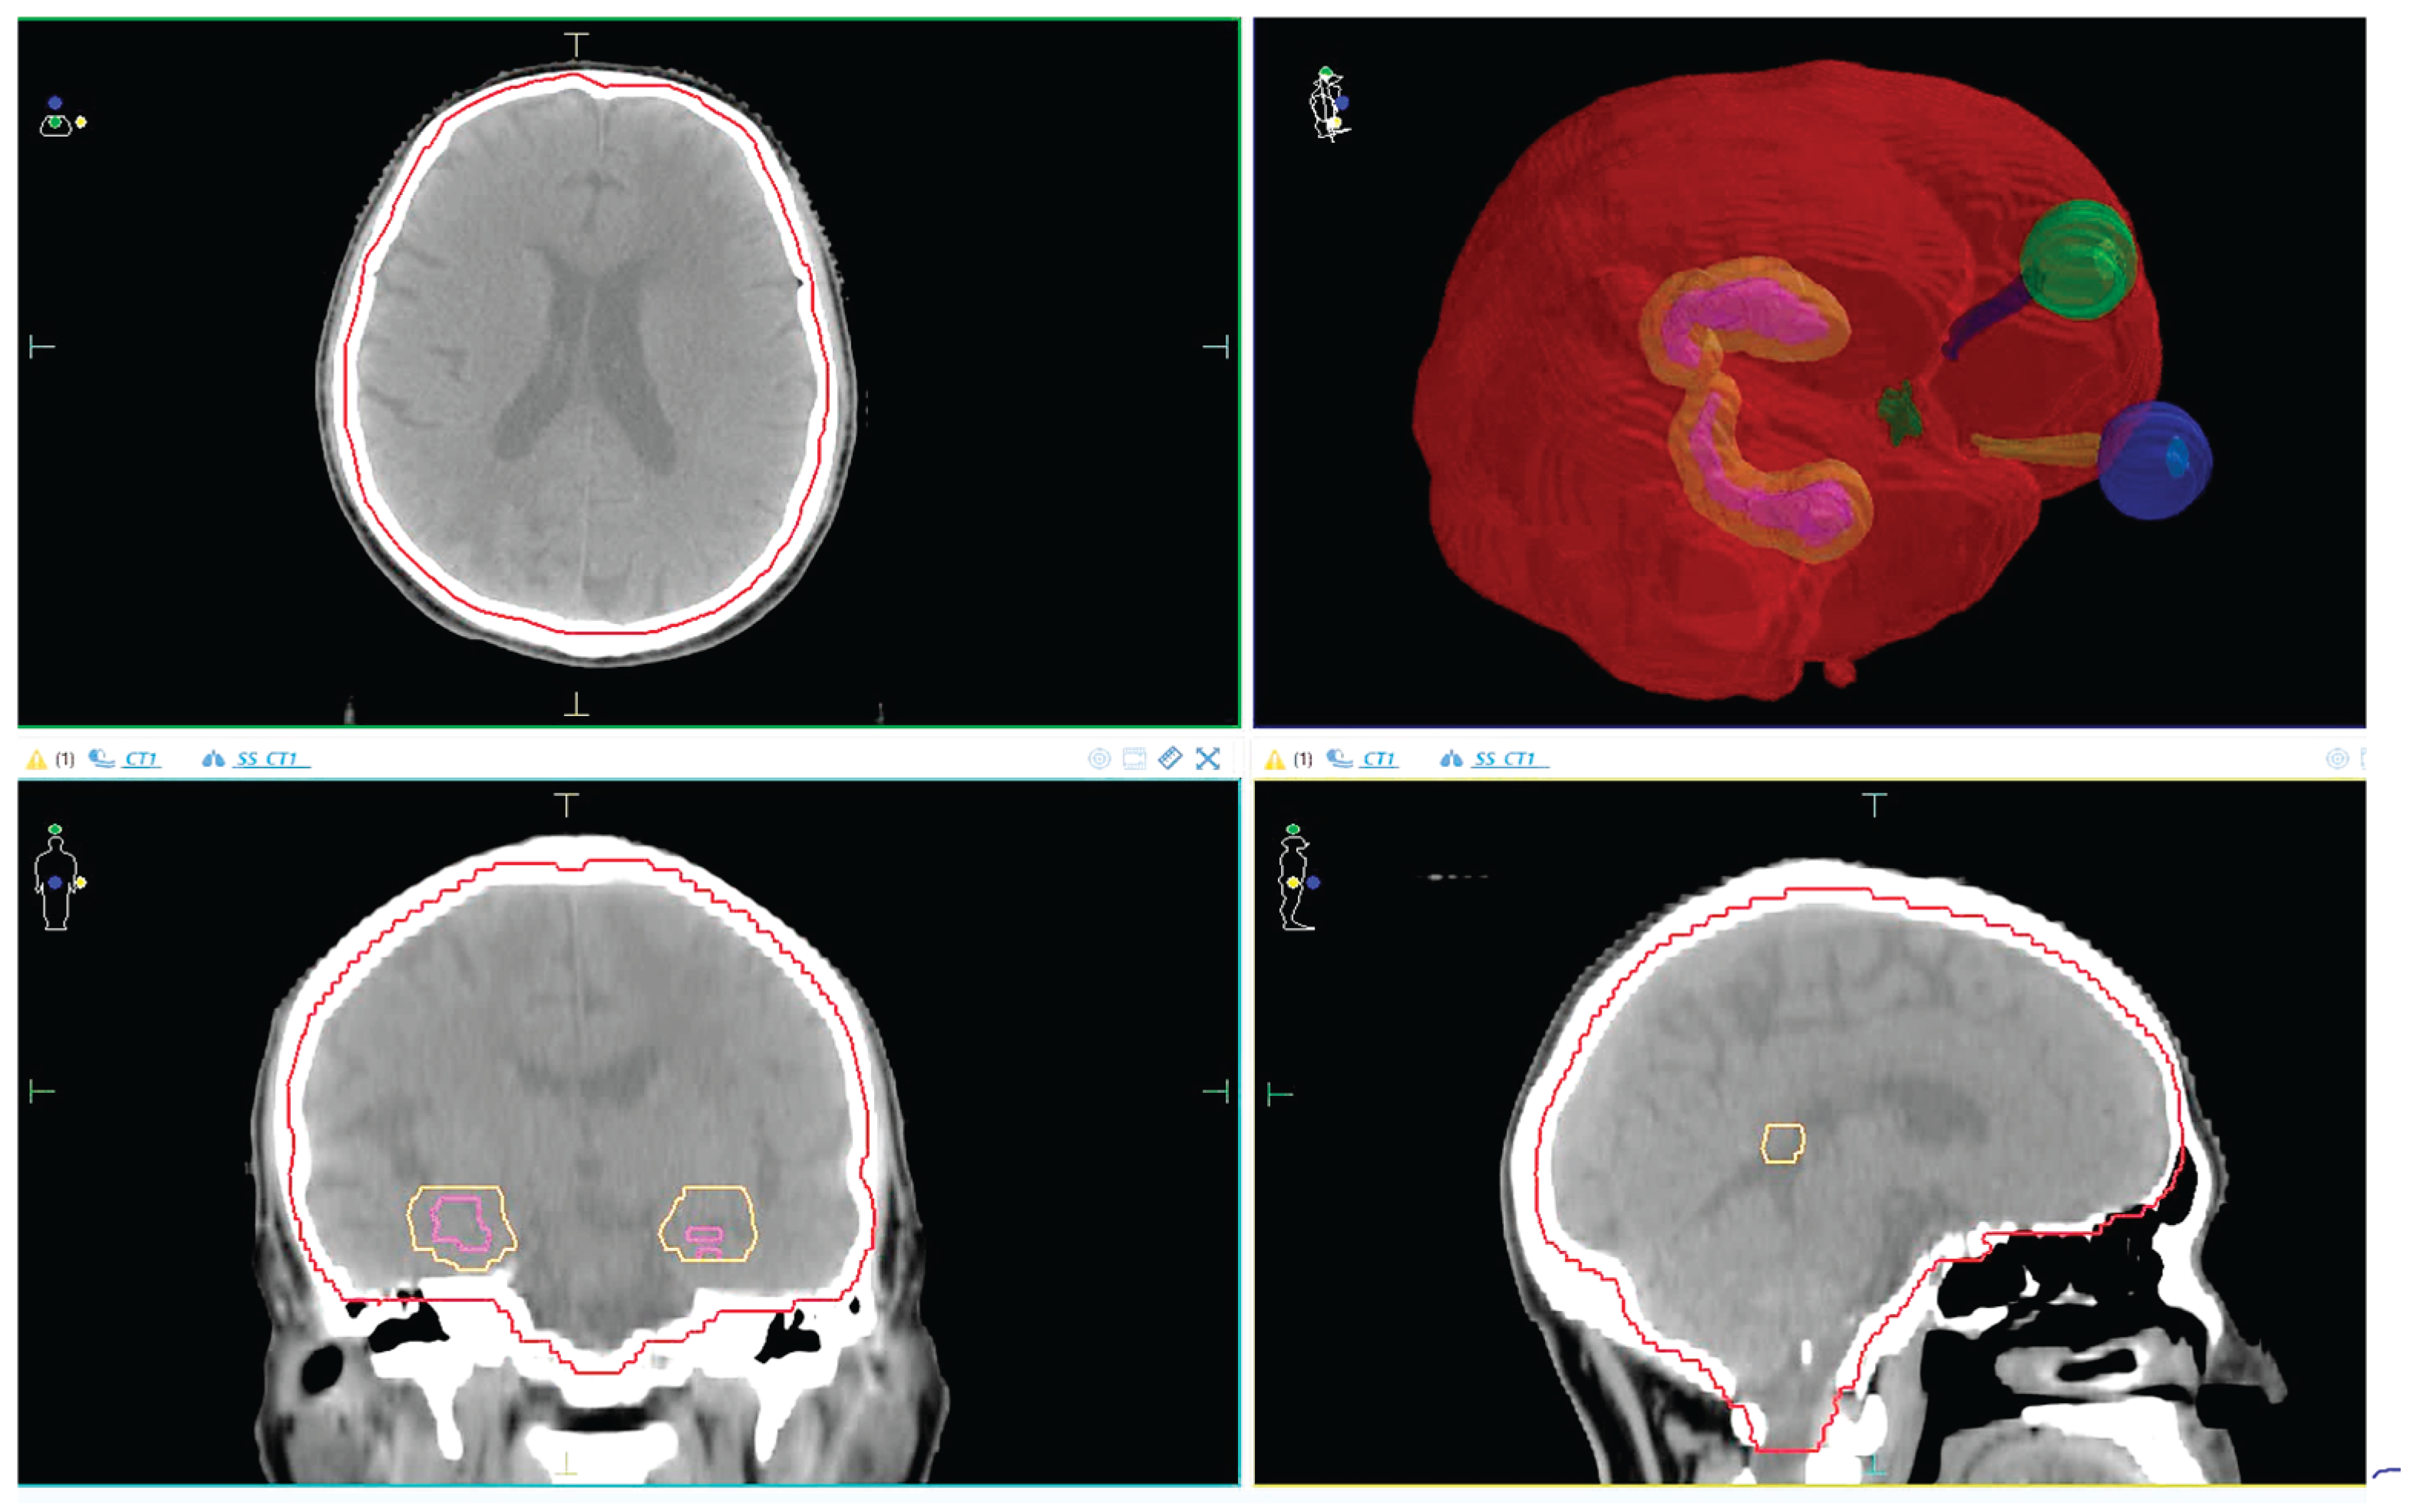

The anatomical relationship between the PTV and surrounding OARs, including the hippocampus and avoidance zone, is illustrated in Figure 1. This visual reference helps clarify spatial planning constraints and margin definitions used in this study.

Figure 1. PTV +5mm and OARs location (The red line represents the PTV, the yellow line represents the hippocampus +5mm margin, while the remaining structures indicate the eyes and optic nerves.).